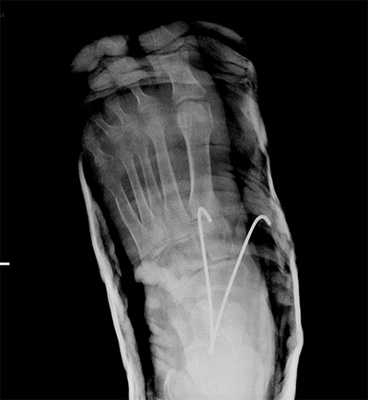

Пациент М. 1980 г.р., травму получил при падении на стопы с высоты 1,5 метра. Лечился по месту жительства (в травмпункте районной больницы) консервативно в гипсовой повязке в течение 14 дней. Консультирован в травматологическом отделении ФГБУ «УНИИТО им. В.Д. Чаклина» Минздрава РФ, предложено оперативное лечение. При поступлении кожные покровы стопы чистые, без признаков воспаления и сдавления тканей. Стопа отечна, уплощена. На рис. 1 представлены рентгенограммы пациента. Прооперирован через 2 недели после травмы. Операция состоит из двух этапов. Первый этап заключается в наложении дистракционного аппарата. Проводятся две спицы 1,8 мм во фронтальной плоскости: первая через нижнюю треть диафиза большеберцовой кости, вторая через бугор пяточной кости (рис. 2). Спицы фиксируются в дистракционном аппарате, выполненном из двух полуколец, соединенных между собой двумя телескопическими тягами. Особое расположение полуколец, фиксация спиц на концах полуколец, крепление кронштейнов для телескопических тяг обеспечивает тракцию пяточной кости в необходимом направлении с использованием минимального количества спиц и внешних опор при сохранении необходимого поля обзора для проведения рентгенологического и визуального контроля репозиции и фиксации. Второй этап - закрытая элевация импрессированной суставной поверхности и окончательная репозиция пяточной кости. Через разрез длиной до 1 см по латеральному краю ахиллова сухожилия (рис. 3) в месте его прикрепления к пяточной кости под соответствующий фрагмент подводится элеватор (рис. 4), манипуляцией которым устраняется смещение и выполняется провизорная фиксация спицами 1,5 мм (рис. 5). При сагиттальном раскалывании суставной фасетки целесообразно проведение одного-двух винтов субхондрально (рис. 6). Стержень вводится с дорзальной поверхности пяточной кости по ее оси через разрез до 2 см по предварительно сформированному остеотомом каналу (рис. 7, 8). Далее через проколы кожи с помощью кондуктора (рис. 9) выполняется запирание винтами с латеральной поверхности, внешнее устройство демонтируется. Достигнуто удовлетворительное стояние отломков (рис. 10).

Рис. 7. По оси пятки проводится спица, по которой затем канюлированным сверлом формируется канал для введения стержня

Рис. 8. Вводится стержень на кондукторе. Данная иллюстрация показывает, что компоновка аппарата внешней фиксации не создает помех для кондуктора